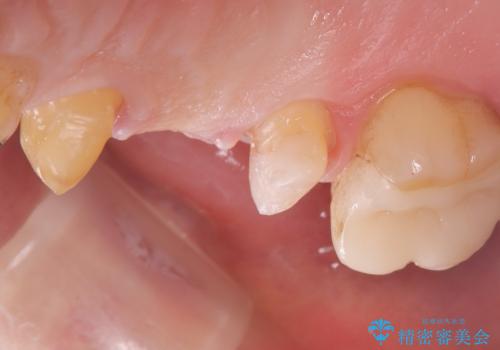

元々5番目の歯には4/5冠が入っていましたが、ブリッジのやり替えに際しクラウンとしました。

右上5はう蝕除去後は間接覆髄を行いCR裏層しています。う蝕が大きく神経症状が出ないか経過を確認しクラウンの印象を行っています。